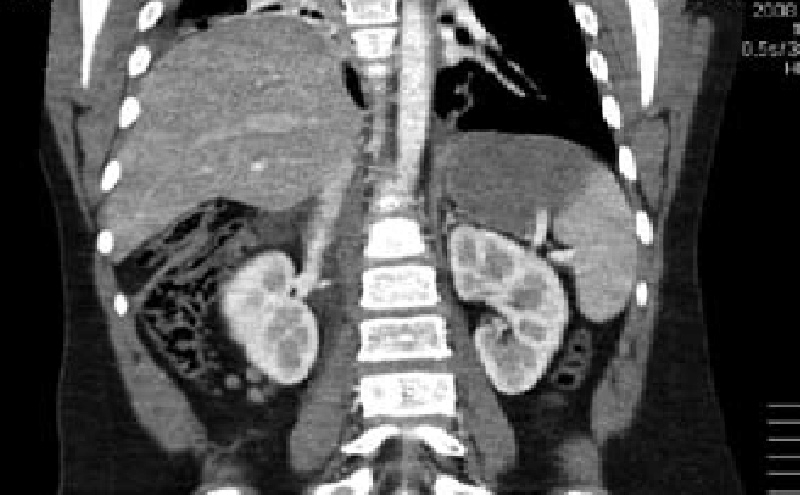

We report a case of a collegiate American style football player presenting to the emergency department with four months of intermittent, non-exertional, midsternal chest pain and pressure. Workup included a computed tomography scan that revealed intrathoracic herniation of the left lobe of the liver through a large Foramen of Morgagni hernia over the right aspect of the heart. Data to guide management is sparse but favors surgical intervention. The patient pursued non-operative management and successfully returned to play to complete a full season of NCAA football as a starting defensive end without complication. This case refutes the common practice of immediate surgical intervention in patients with Morgagni hernias.

A 19 year old previously healthy male, NCAA defensive end, presents with four months of intermittent, non-exertional, midsternal chest pain and pressure. The pain is described as an episodic band like pressure radiating across the epigastrium. At maximum the pain is rated four out of ten and is completely relieved with holding a deep inspiration. There are no other mitigating or exacerbating factors. There are no other associated symptoms. This has never happened previously. Initial workup in the emergency department with chest radiograph revealed a right cardiophrenic angle mass. Electrocardiogram, complete blood count, comprehensive metabolic panel, lipase and troponin were within normal limits. Computed tomography scan revealed intrathoracic herniation of the left lobe of the liver through a large Foramen of Morgagni hernia over the right aspect of the heart. The patient obtained cardiothoracic surgery consultation and opted to forego surgical intervention while symptoms remained mild to moderate. The patient successfully returned to play and completed a full season as an NCAA defensive end without complication. The patient has another year of eligibility and plans to complete his collegiate career without surgery if symptoms remain stable.